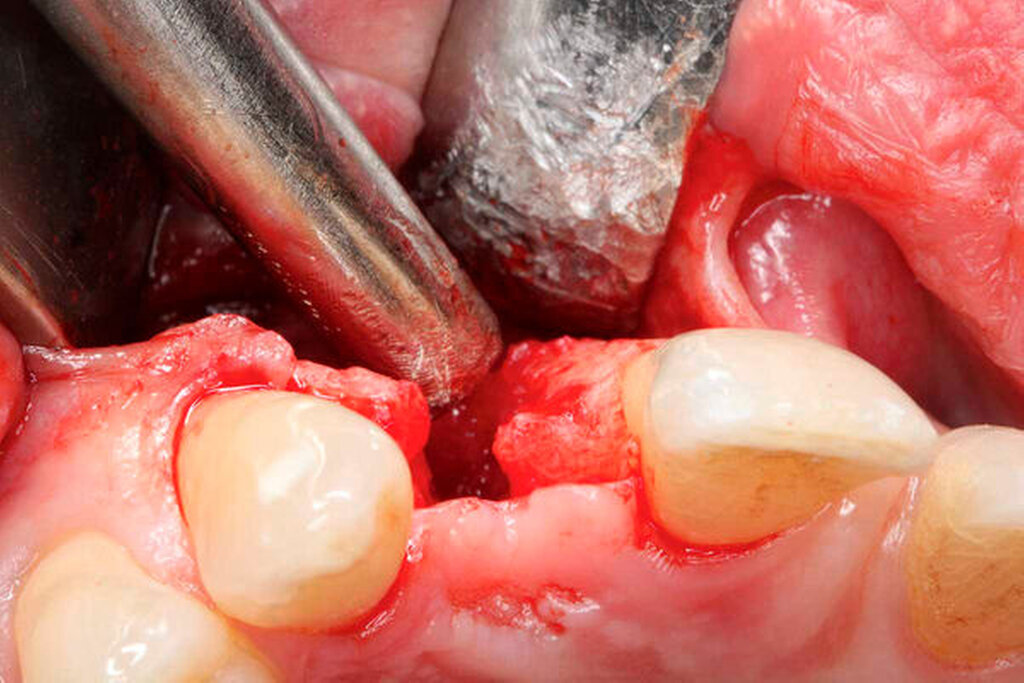

Zahnaufbereitung: Nach der Extraktion des Zahnes 18 folgte die Entfernung von Debris sowie des Parodontalligaments von der Wurzeloberfläche mit einem grobkörnigen Diamantschleifer unter Wasserkühlung (Abbildung 2a). Mittels einer diamantierten Trennscheibe (Frios MicroSaw, Dentsply Sirona Implants, Mannheim, Deutschland) wurde unter Wasserkühlung eine circa 1–1,5 mm starke Dentinscheibe gewonnen (Abbildung 2b). Das restliche Dentin wurde mit einem sterilen Einweg-Mahlwerk (Smart Dentin Grinder, Kometa Bio, Creskill, USA) in 300–1200 μm große Dentinpartikel zerkleinert (Abbildungen 2c und 2d). Die Dentinscheibe und das Partikulat wurden anschließend chemisch mit antibakteriellen Lösungen aufbereitet. Abschließend erfolgte eine partielle Demineralisierung des Dentins zur Freilegung des Kollagennetzwerks und zur Freigabe osteoinduktiv wirksamer Wachstumsfaktoren [Y. K. Kim et al., 2014]. Die Zahnaufbereitung erfolgte simultan zum implantologischen Eingriff regio 22.